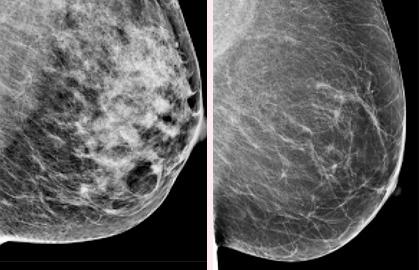

Long-term use of constrictive bras, hormone replacement therapy, disrupted circadian rhythm, air pollution, and sedentary lifestyle do not directly destroy breast tissue. Instead, they cause persistent accumulation of estrogen metabolites, necrotic cells, and inflammatory factors within lymphatic vessels, resulting in irreversible blockage. Clinical data show that women over 50 have an average lymphatic flow rate of only 27% compared to younger ages. Localized induration, increased mammographic density, and unexplained masses are all typical manifestations of this chronic obstruction. Conventional interventions only alleviate surface symptoms and cannot remove deep deposits.